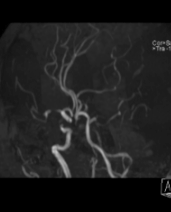

10 分钟后,手术顺利完成,堵塞血管成功开通,濒临坏死的脑细胞被及时 “救回”,张女士的病情得到了有效控制。